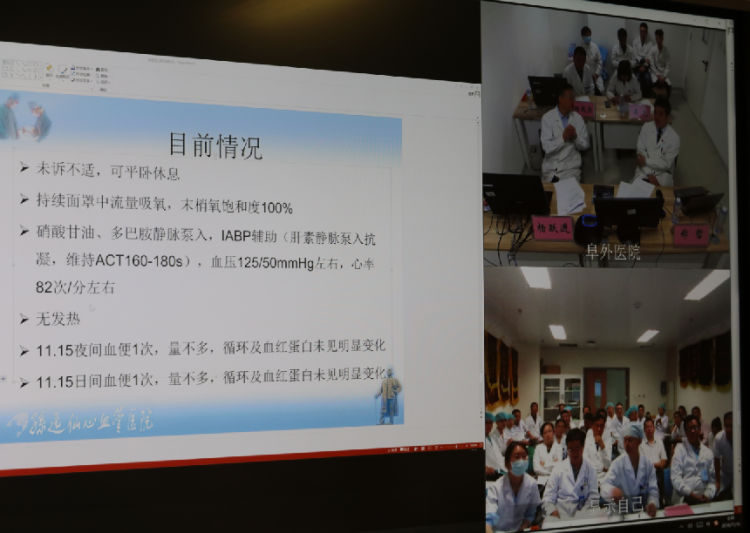

首例会诊患者因“急诊PCI术后冠脉急性闭塞、室壁瘤形成、室间隔穿孔”于11月5日从外院转入我院治疗,住院第二天即心衰症状加重急行IABP植入术。患者各项指标经治疗后逐渐好转,但检查发现其再发心梗、室间隔穿孔明显扩大。考虑到患者病情较为复杂,手术存在较大风险,为保障患者安全和医疗质量,经医院内病例讨论决定紧急邀请阜外医院专家提供技术支持,并顺利在我院ICU连线完成远程多学科疑难病例会诊讨论。

会诊由医务部王湘主任主持,阜外医院副院长、阜外深圳医院副院长杨跃进教授,阜外医院郑哲副院长、CCU主任吴元教授、医务处杨国胜处长组成北京会诊专家组,阜外深圳医院李惠君院长、心内科专家屠洪教授、副院长陈伟新教授、ICU温隽珉主任、外科魏民新主任、杨晓涵主任、麻醉科黄志勇主任、放射科袁旭春主任、超声科钟新波主任等十余名专家共同参与。在充分了解病人病情及现有诊疗方案后,各位专家展开了深入交流及讨论,最终形成一致意见,为病人下一步诊治提出了有针对性的解决方案。